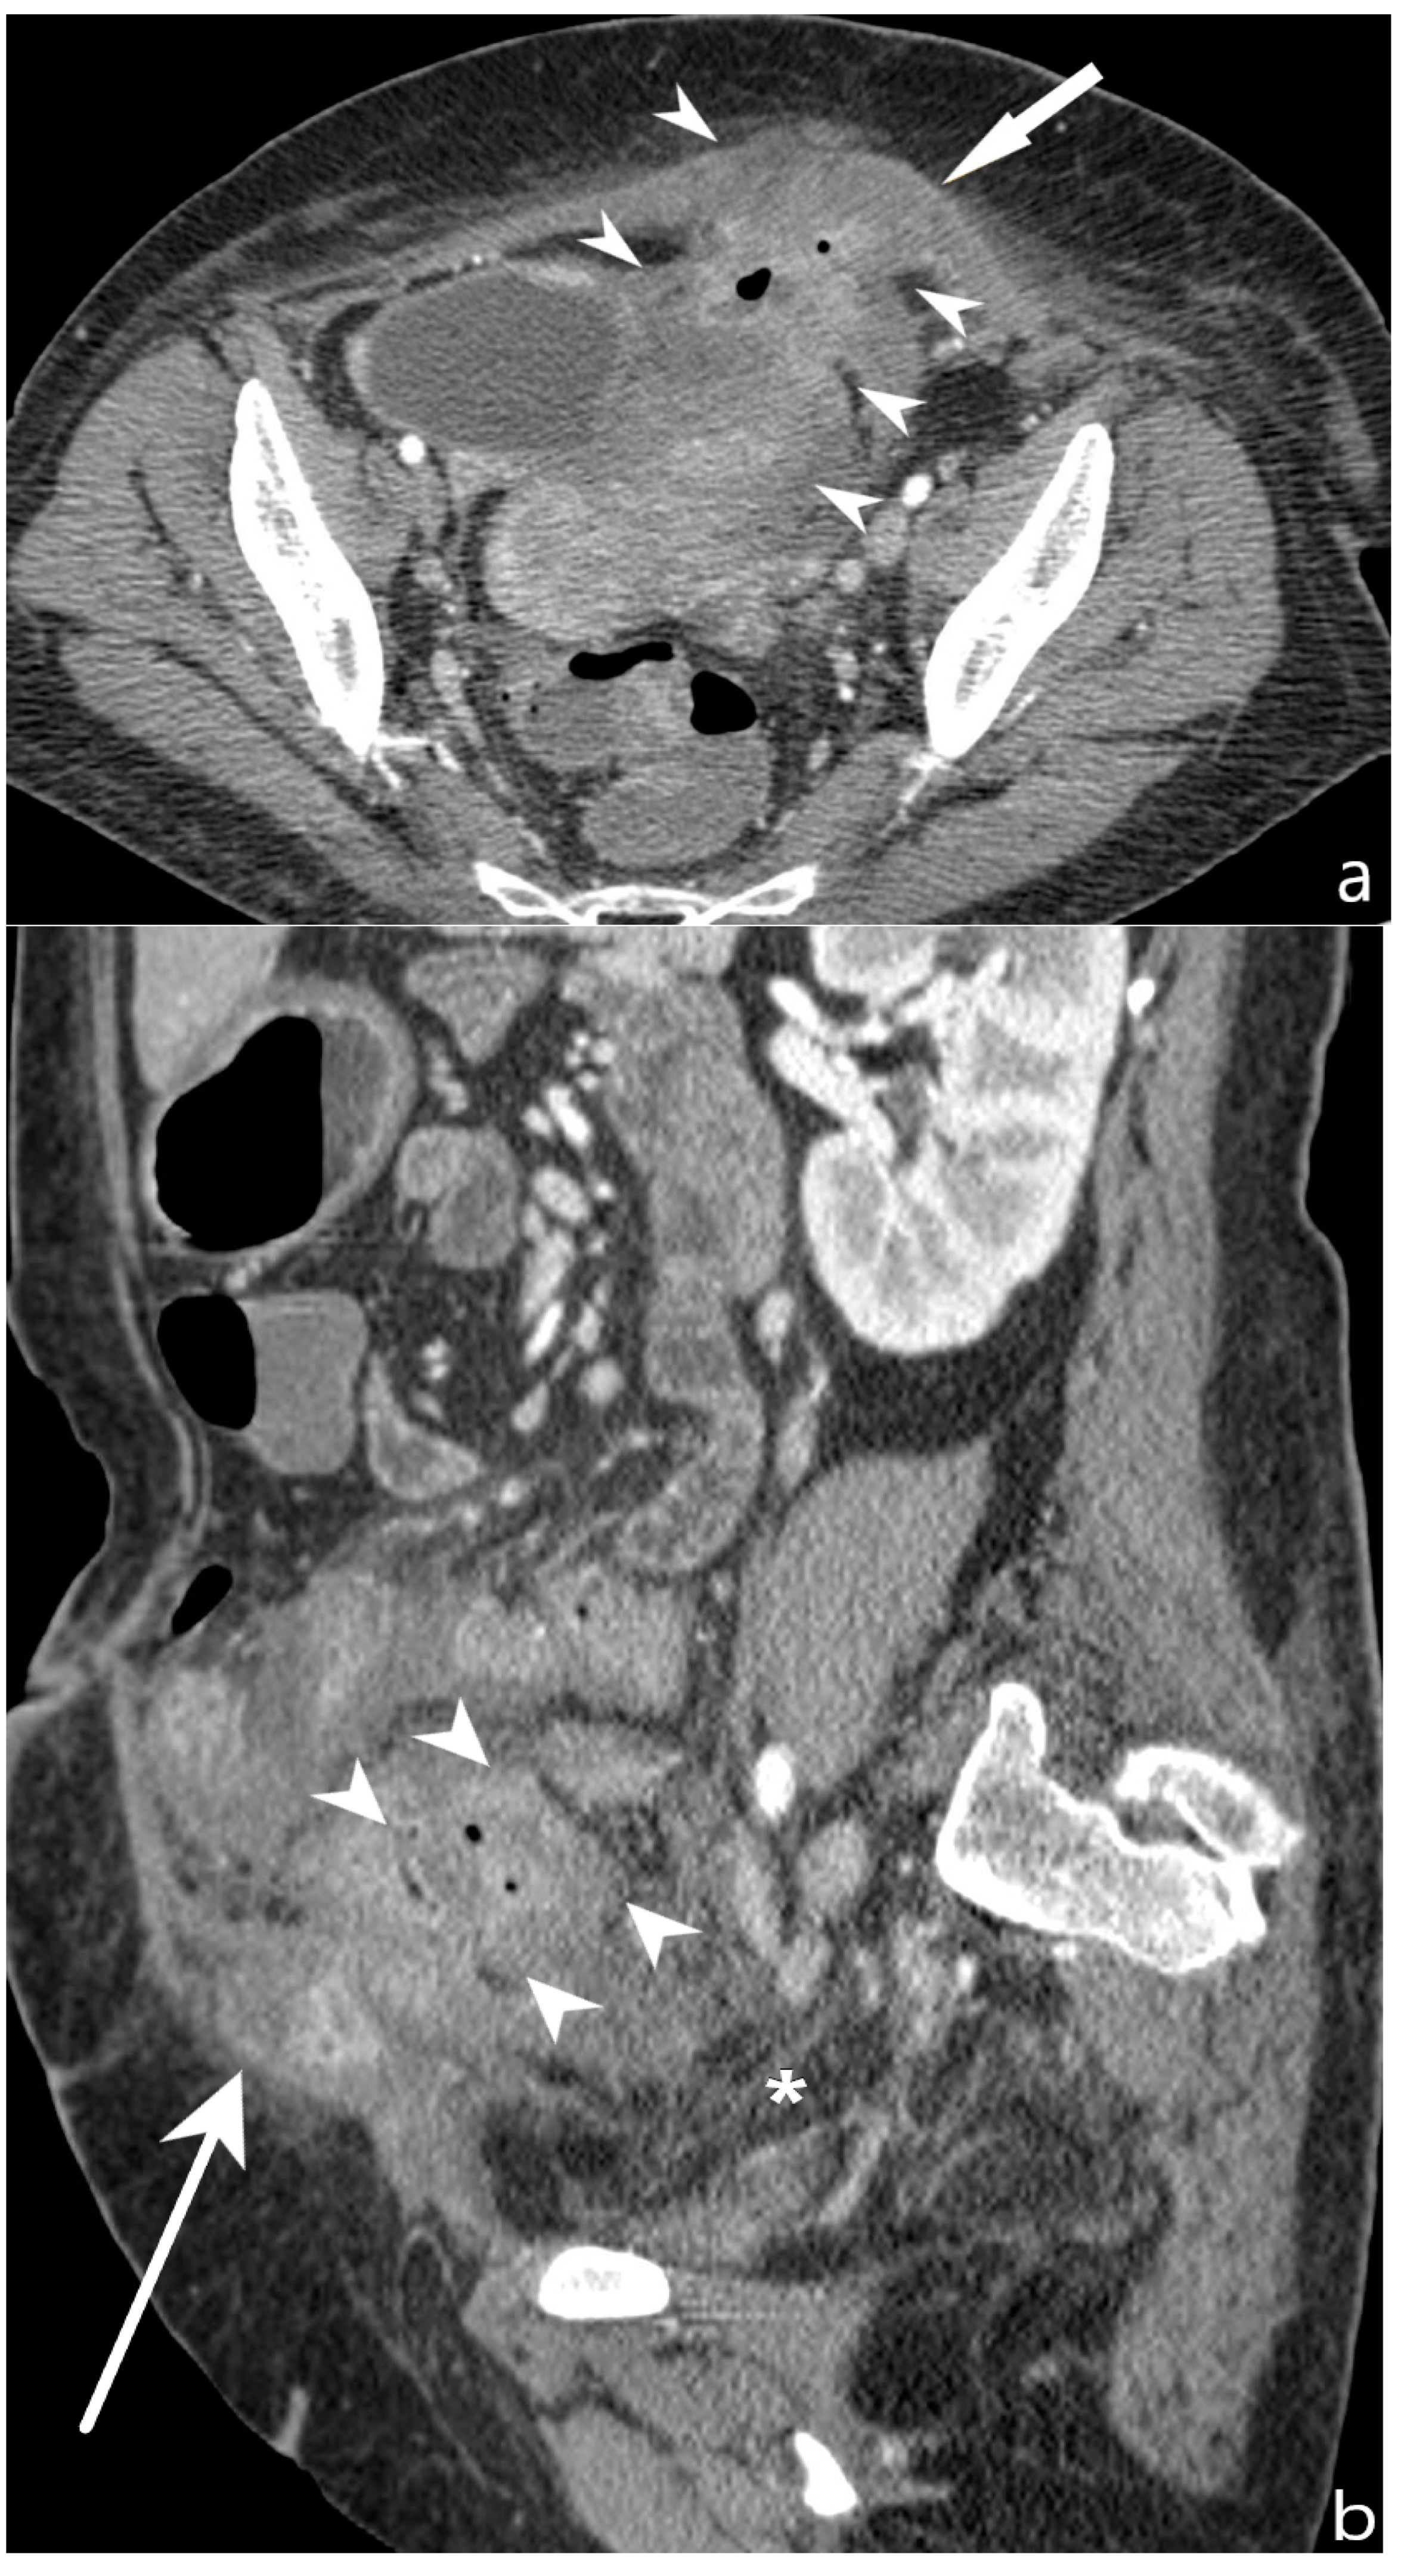

5.2. Fibro-Stenotic Subtype

6. Is It Possible to Identify the Presence of Strictures and to Discriminate Inflammatory from Fibrotic Ones?

6.2. Differentiation between Fibrotic or Inflammatory Stenosis